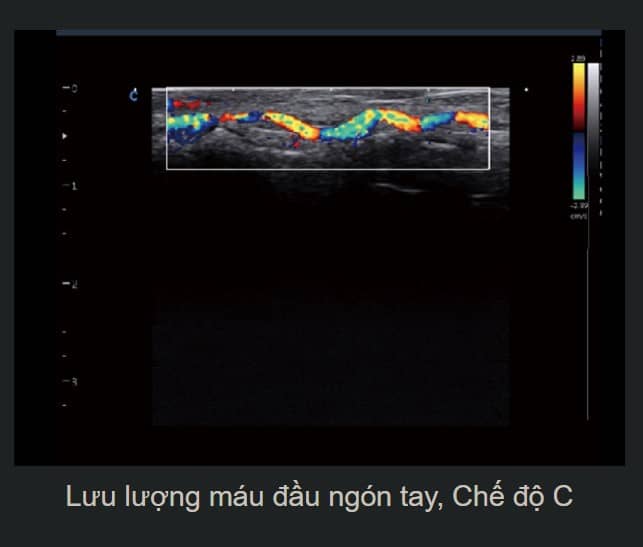

- Hình Ảnh Toàn Cảnh Màu: Phóng to vùng quét và cung cấp nhiều thông tin về màu sắc, đặc biệt hữu ích cho việc phân tích mạch máu lớn.

- SonoColor và SonoContrast: Cung cấp phân tích dòng định lượng và độ nhạy cao hơn, thích ứng với mọi loại đầu dò.